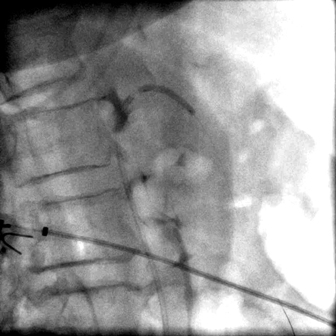

Ангиография. Этап баллонной дилатации верхней брызжеечной артерии.